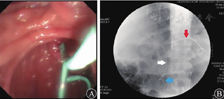

患者入院2周(恢复期)后病情较平稳。2019年10月21日,患者出现发热,体温最高达39.0 ℃,应用美罗培南(0.5 g/次,3次/d)和替加环素(50 mg/次,2次/d)抗感染治疗后,患者体温逐渐恢复至36.5 ℃。2019年10月29日复查CT示胰腺假性囊肿增大,随后患者出现中腹部胀痛、恶心等压迫症状,经多学科讨论后于11月19日行超声内镜引导下经胃胰腺假性囊肿金属支架置入术(图2),术中采集引流液进行细菌培养,等待药敏试验结果期间继续予美罗培南(0.5 g/次,3次/d)和替加环素(50 mg/次,2次/d)抗感染治疗,2019年11月21日(支架置入2 d后)常规行胃镜下经金属支架胰腺坏死组织清除术(图3),术后患者生命体征平稳。2019年11月22日凌晨4:00患者无明显诱因突发呕血,呕吐量约500 mL的鲜红色液体;排暗红色血便1次,量约150 mL;伴心悸、出冷汗,血压为80/50 mmHg,急查血常规示白细胞计数为19.65×109/L,红细胞计数为3.29×1012/L,血红蛋白为105 g/L,急诊CT检查示胰周包裹性积液和积血。急诊胃镜检查示囊肿支架内附着大量血凝块,予拔除金属支架,未见活动性出血(图4),立即行腹腔数字减影血管造影,预防胰大动脉和胰背动脉栓塞,同时予输血和止血等对症支持治疗,患者未再发生活动性出血。

单猪尾支架怎么放重症急性胰腺炎合并出血性休克和感染性休克_https://www.jmylbn.com_新闻资讯_第3张

图2 2019年11月19日行超声内镜引导下双头金属支架引流假性囊肿

A 支架释放 B 支架定位(箭头所示)